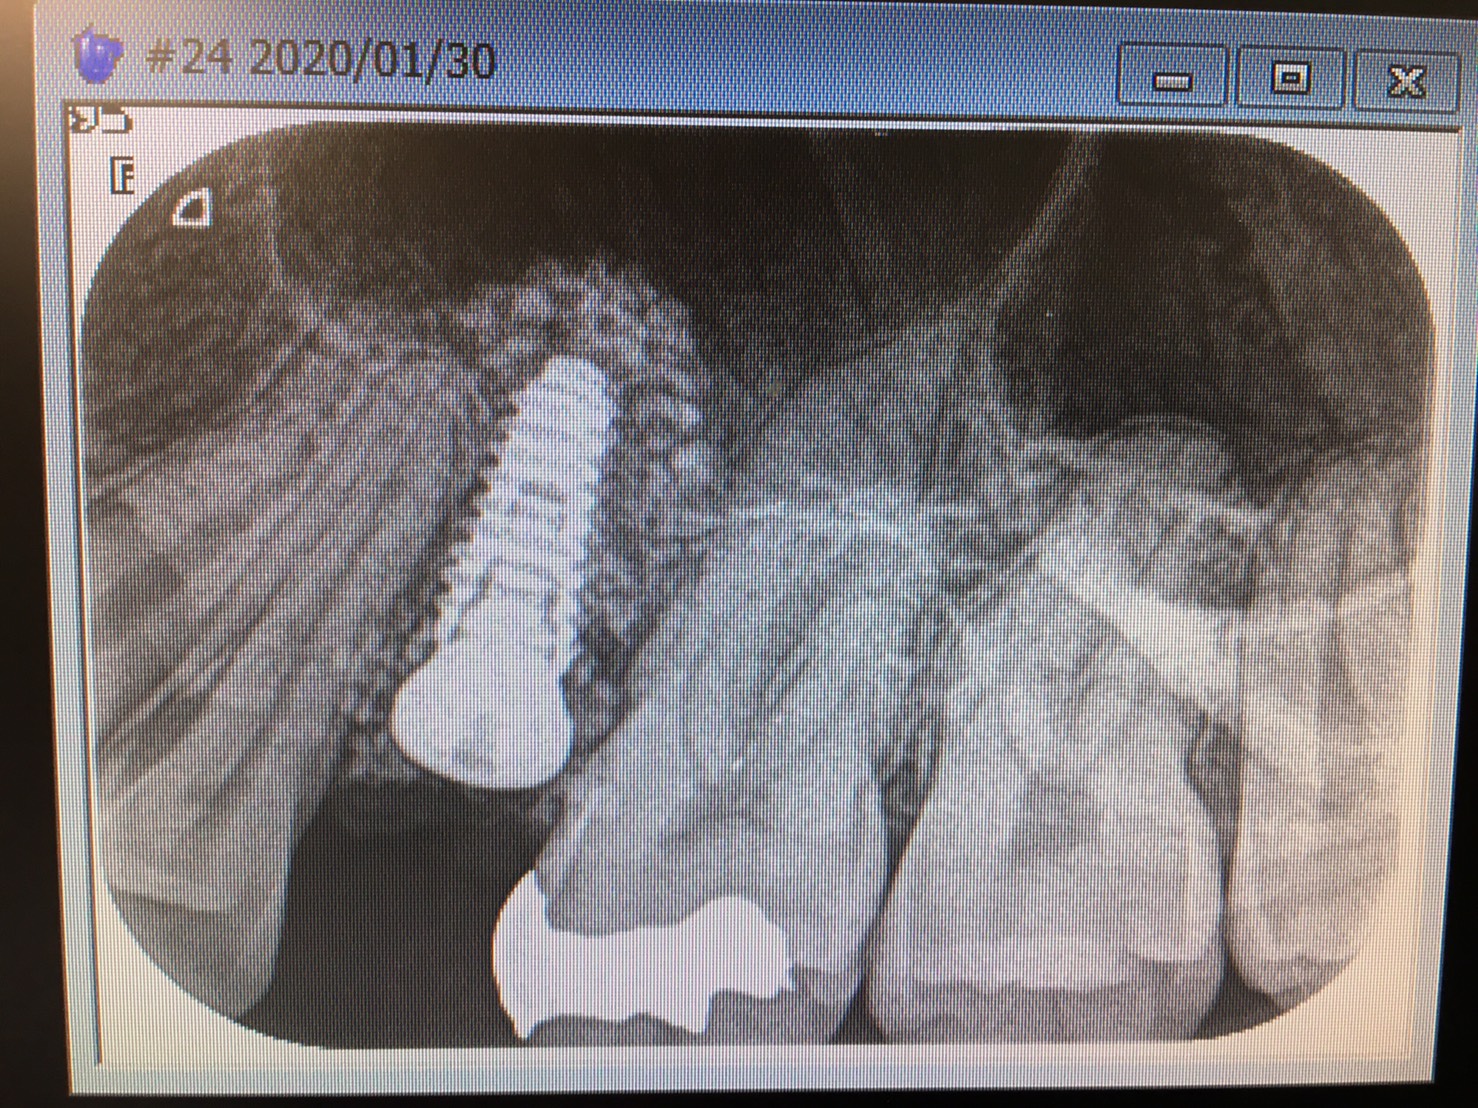

本日は浅草橋分院にて須田理事長のインプラントオペ 部位は左上5番ソケットリフト 残存骨高さは2ミリから5ミリのスロープ形態の難易度高いオペです スリットやらベント等の穴を始めに作りアプローチ窩からも膜を剥離し5ミリ位の挙上が得られバッチリですね! 術前の3D画像からも、難しさが分かります